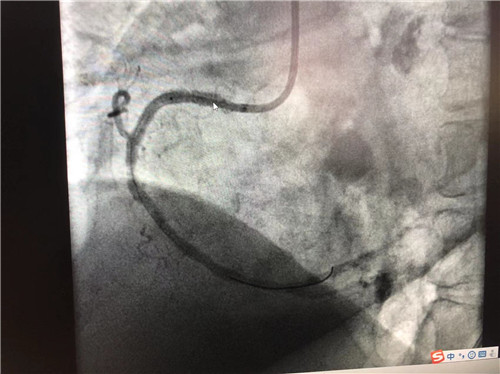

時間就是心肌,時間就是生命。導(dǎo)管室內(nèi),心血管內(nèi)科副主任徐先進(jìn)、主任助理農(nóng)彥林已然待命,病人一到,團(tuán)隊立即為其行深靜脈穿刺泵入血管活性藥物等,情況緩解后,行多體位冠狀動脈造影,確認(rèn)RCA(右冠狀動脈)近端完全閉塞。經(jīng)家屬同意,在汪念東院長的指導(dǎo)下,徐先進(jìn)、農(nóng)彥林、張星為患者行經(jīng)皮冠狀動脈球囊擴張成形術(shù)+經(jīng)外周靜脈穿刺中心靜脈置管術(shù)。術(shù)中,張奶奶再次出現(xiàn)室顫,心血管內(nèi)科團(tuán)隊臨危不亂,立即予以300焦電除顫搶救,患者竇性心律恢復(fù)。隨后,球囊擴張為其置入心臟支架,復(fù)查造影顯示血管恢復(fù)暢通,無明顯夾層,殘余狹窄不到10%。術(shù)后,張奶奶血壓偏低,轉(zhuǎn)入ICU無創(chuàng)呼吸監(jiān)護(hù),2天后轉(zhuǎn)回心血管內(nèi)科護(hù)理。

術(shù)后